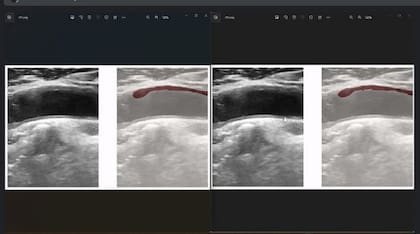

Al igual que en otras áreas de la salud, el rápido desarrollo de la inteligencia artificial encuentra aplicaciones en diversos campos, en este caso como asistencia a quienes deben realizar diagnósticos. El proyecto “Inteligencia artificial para prevenir enfermedades cardiovasculares”, una iniciativa conjunta entre la empresa Eira Healthcare e investigadores del Instituto de Investigación de Ciencias de la Salud (INICSA) de la Universidad Nacional de Córdoba y el CONICET, está desarrollando una técnica de inteligencia artificial para detectar riesgo cardiovascular en diagnóstico por imágenes. A partir del trabajo en conjunto se desarrolló un software que asiste a los médicos en la detección de arterioesclerosis cardiovascular en el análisis de las ecografías de carótida y cruzando información con otras variables de la consulta.

La arterioesclerosis es una afección en la que una placa formada por grasa, colesterol y calcio, entre otras sustancias, se acumula en las paredes de las arterias y con el tiempo se endurece, con lo que reduce el flujo de sangre por los vasos pudiendo generar infartos. Por eso, determinar el área total que ocupa la placa es vital para prevenir posibles problemas de salud. El software busca evitar uno de los limitantes más importantes de la técnica de diagnóstico, que es la variabilidad de los resultados obtenidos a partir de las imágenes, que dependen del técnico operador del ecógrafo, y así ayudar en la detección temprana y en el monitoreo de factores de riesgo.

El desarrollo ya está en su etapa final de entrenamiento del algoritmo y pronto presentará resultados preliminares. Gilda Romero es la responsable del proyecto por parte de la Fundación Sadosky: “Se le están haciendo estudios a pacientes que tienen determinadas características de historia clínica y el médico le va marcando cosas al sistema para que el algoritmo pueda reconocer esas imágenes. Esto permitirá tener una identificación más certera del riesgo que dependa menos de la experiencia de quien maneja el ecógrafo”.

Las tres etapas del proyecto

El proyecto tuvo una primera etapa en la que se desarrolló el software, una segunda etapa en la que se cargaron imágenes para entrenar al modelo en las diversas formas en que se toman imágenes por parte de diferentes operadores de ecógrafo, y una tercera en la que se cargan en forma masiva las imágenes para que la inteligencia artificial pueda determinar el riesgo cardiovascular. Se trata de una técnica novedosa y se espera que facilite el diagnóstico de estas afecciones.